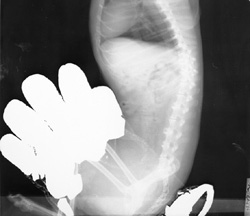

Hands in Primary Beam